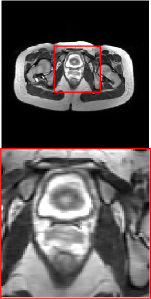

Figure 5 provides the qualitative comparison of the various methods on the four datasets at a scale of 4. The top, second, third, and bottom rows are the SR results under the FastMRI, clinical brain, clinical tumor and clinical pelvic datasets, respectively. The red boxes indicate the zoom-in region of complicated anatomical structures along with their corresponding error maps. Note that the brighter textures in the error maps, the lower the quality of the reconstructed images. As can be seen, compared to methods based on Transformers and CNNs, diffusion-based methods like DisC-Diff and DiffMSR (Ours) are capable of reconstructing high-realistic images with promising reconstruction metric scores (PSNR and SSIM). Nevertheless, while DisC-Diff can reconstruct high-precision MR images, it does not preserve the structure present in the original HR images, introducing some additional information that can affect medical diagnosis. In contrast, our method combines DM and PLWformer, which can preserve the original image’s structure while restoring high-frequency information.

In this section, we present more visual qualitative comparisons. Figures 8, 9, 10, and 11 show the reconstruction results of each method in FastMRI, clinical brain, clinical tumor, and clinical pelvic, respectively. As can be seen, although DisC-Diff can reconstruct MR images with high-frequency information, it fails to preserve the structure and content of the original Target HR image effectively, resulting in image distortion. In contrast, our proposed DiffMSR can restore high-frequency information while preserving the structure of the original HR image, indicating the effectiveness of the joint use of DM and PLWformer.